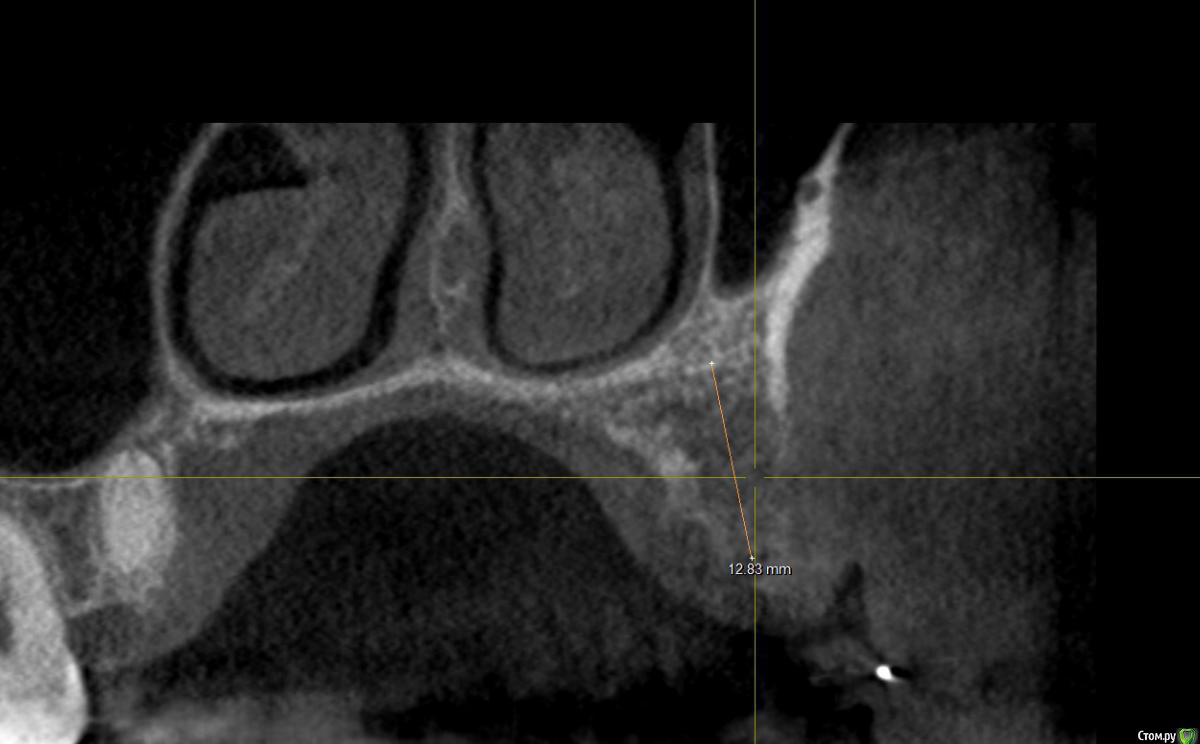

Al..ks Опубликовано 18 апреля, 2019 Поделиться Опубликовано 18 апреля, 2019 Добрый день. Планируется имплантация(15 или 14. брекеты ношу, поэтому не знаю какой будет)+аугментация (в области кармана 17 и при имплантации в случае недостатка кости)+пластика десны+установка формирователя. Все за раз.На выбор dentium, Astra, Nobel, Straumann. Подходят любые и выбор за мной(я склоняюсь к Астре). Правильный выбор? . Плюс ко всему по КТ там отсутствует кортикальный слой( по словам врача) я так понял с наружней стороны, поможет ли аугментация?И поможет ли она с карманом 17? И так как двигали зубы в области корня 11 появилась пустота (толи уже было)в середине лечения и на данный момент Надо ли делать резекцию корня - или канал перелечивать (там ставили СВШ перед брекетами) перед протезирование? Ссылка на комментарий

Al..ks Опубликовано 19 апреля, 2019 Автор Поделиться Опубликовано 19 апреля, 2019 Правильный Аугментация с карманом не поможет. В остальном - да Нужно сравнить КТ начала лечения и последнее. Рентгенологически, канал 11 пролечен хорошо. Возможно, это остаточные явления.Спасибо за ответ. В отношении 17 мне планировали там подрезать десну (типо лучше будет возможность чистить и дольше зуб сохранить. Хотя думаю чувствительность поднимется блин(() и этот материал использовать для пластики десны у 16 и заодно подсыпать туда костного материала .Хотя когда еще давно (года три назад) удаляли 18 и чистили там грануляции, стенки между 17-18 не было.И там уже был этот карман и ничем закрыть его нельзя - пустая трата денег и кость вниз не нарастет. Хорошо хоть подвижность уменьшилась - наверное благодаря брекетам). Не нанесет ли вред аугментация зубу 17? Ссылка на комментарий

suballex Опубликовано 19 апреля, 2019 Поделиться Опубликовано 19 апреля, 2019 Спасибо за ответ. В отношении 17 мне планировали там подрезать десну (типо лучше будет возможность чистить и дольше зуб сохранить. Хотя думаю чувствительность поднимется блин(() и этот материал использовать для пластики десны у 16 и заодно подсыпать туда костного материала .Хотя когда еще давно (года три назад) удаляли 18 и чистили там грануляции, стенки между 17-18 не было.И там уже был этот карман и ничем закрыть его нельзя - пустая трата денег и кость вниз не нарастет. Хорошо хоть подвижность уменьшилась - наверное благодаря брекетам). Не нанесет ли вред аугментация зубу 17?Нет, не нанесет. Возможно, наступит временное улучшение. Через какое то время вернетесь к изначальной ситуации. Ссылка на комментарий